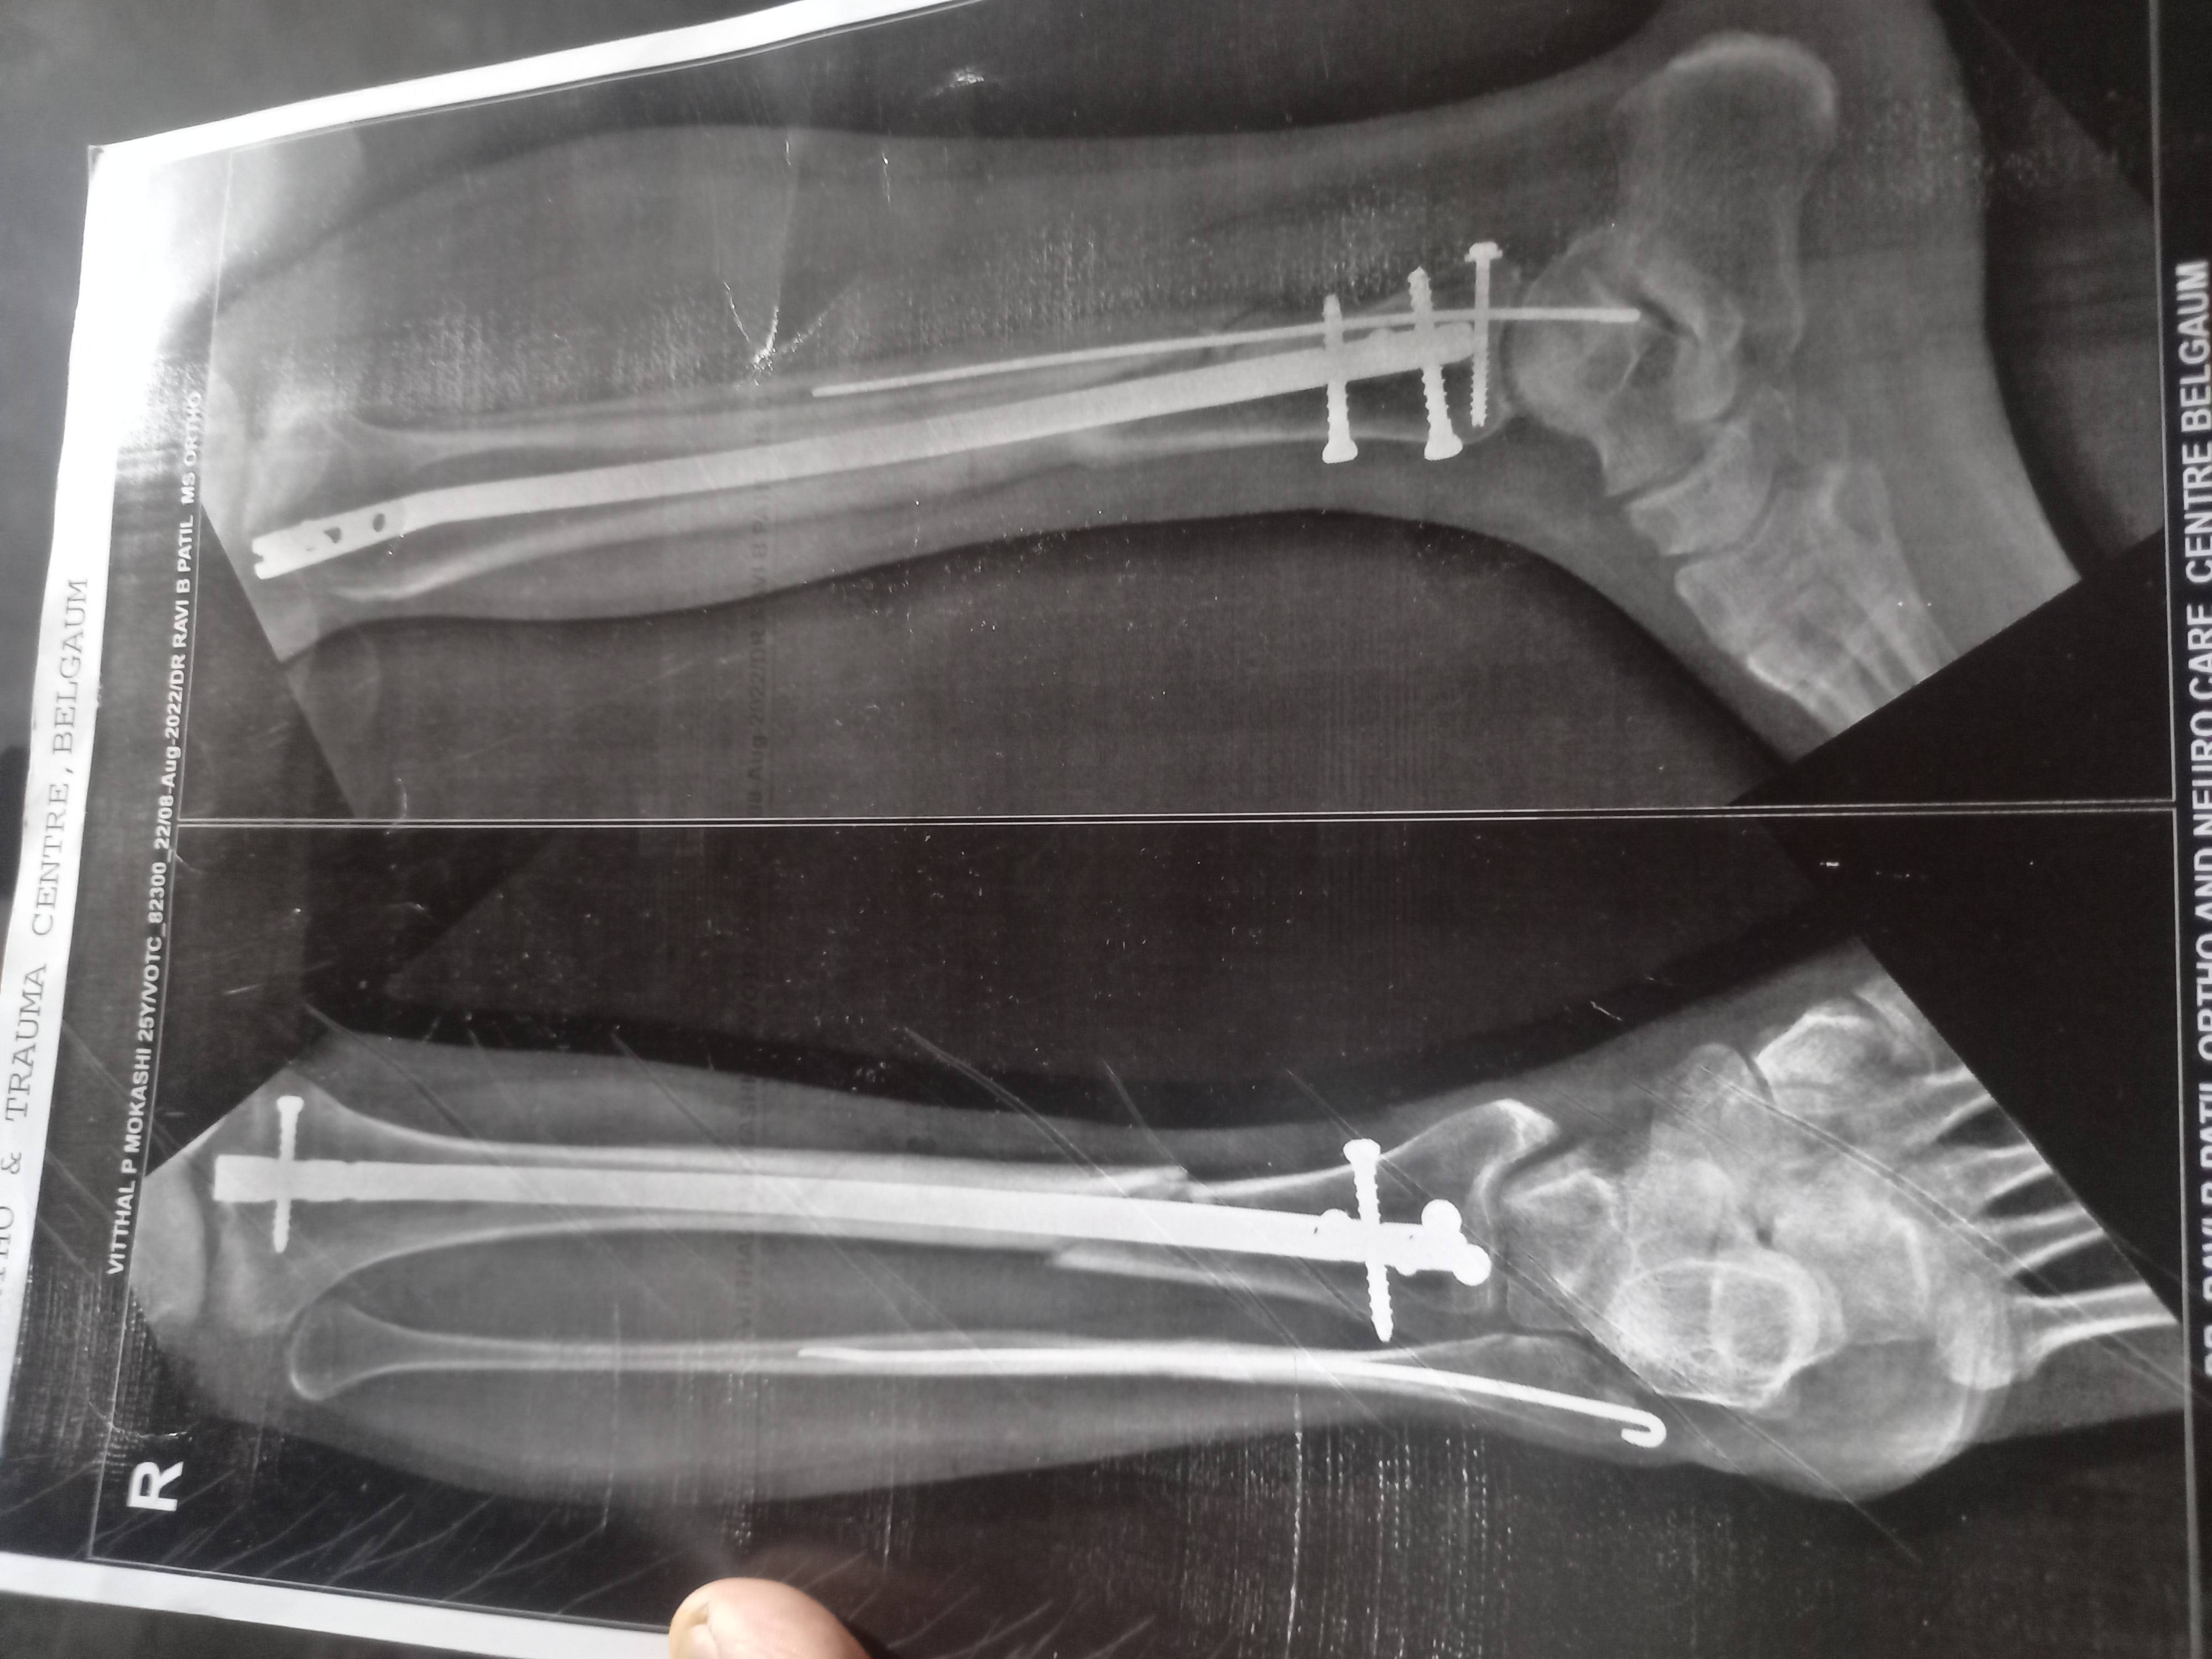

Vithal mokashi

. Following